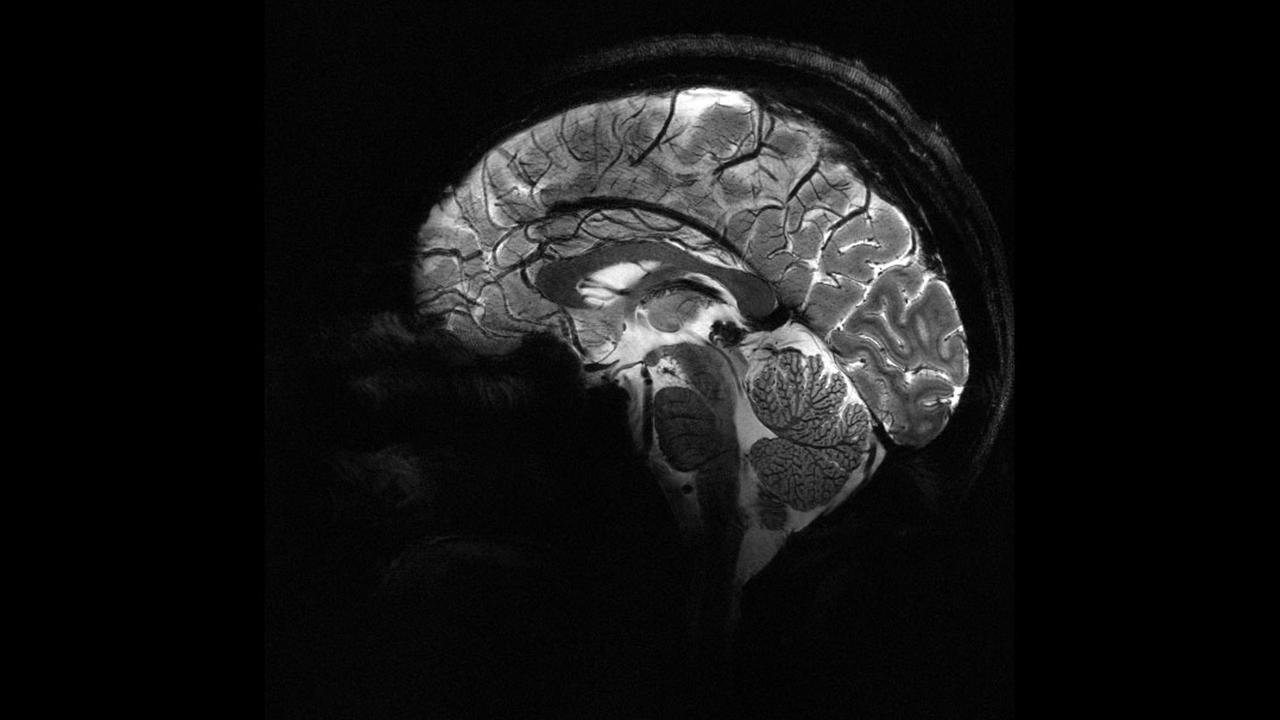

Deney sırasında beynin ön ve arka kısımlarında yer alan frontal ve paryetal bölgelere elektrik akımı uygulandı. Bu iki bölge aynı anda uyarıldığında, katılımcıların daha fazla para paylaştığı gözlemlendi.

Bu çalışma, katılımcıların para paylaşma oyunu sırasında beyin aktivitelerinin izlendiği önceki bir araştırmaya dayanıyor. Önceki çalışmada, daha fazla para paylaşıldığında beynin karar verme ve empati bölgelerinin aynı frekansta “iletişim kurduğu” tespit edilmişti. Yeni deneyle birlikte, dışarıdan müdahale ile bu bölgeler arasındaki iletişimin tetiklenebileceği ve insanların daha özverili kararlara yönlendirilebileceği kanıtlanmış oldu.

Araştırma ekibinden Dr. Jie Hu, çalışmanın en yeni yanının neden-sonuç ilişkisini ortaya koyması olduğunu söyledi. Hu, hedeflenmiş ve cerrahi müdahale gerektirmeyen bir stimülasyonla belirli bir beyin ağındaki iletişimin değiştirilmesinin, insanların kendi çıkarları ile başkalarının çıkarları arasındaki dengeyi nasıl kurduklarını doğrudan etkilediğini vurguladı.